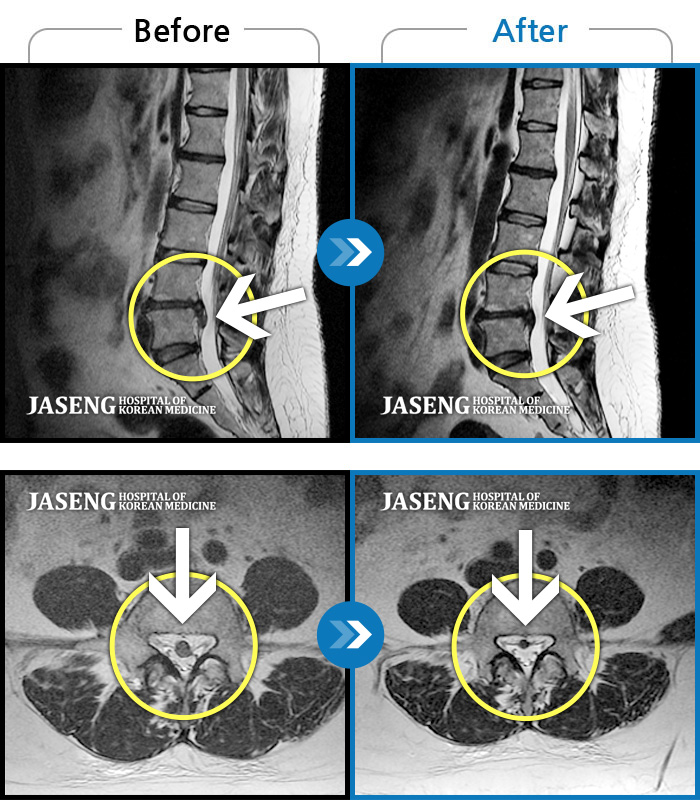

Before

After

환자에게 사전 동의를 받아 동일 조건에서 촬영되었습니다.

개인에 따라 치료 후 부작용이 발생할 수 있으니 의료진과 상담 후 치료를 진행하시기 바랍니다.

허리통증, 좌측 다리 바깥쪽으로 저림이 있어서 양말을 신기도 어려워요.

양측 허리부터 골반 통증, 좌측 종아리까지 이어지는 당김